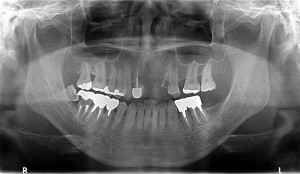

以前、当院で左上7番部にインプラントを埋入させて頂いた既往のある方でした。

左上6番がかなり動揺していたので抜歯をし、

4ヵ月経過したのでCT画像を拝見させていただきました。

十分に骨は再生しているようでしたが、

上顎洞底骨の厚みは4mmほどしかなかった為、

ソケットリフトを併用してオスフェリオンを填入後、

日本製マイティスアローインプラントB4008sfを埋入させて頂きました。